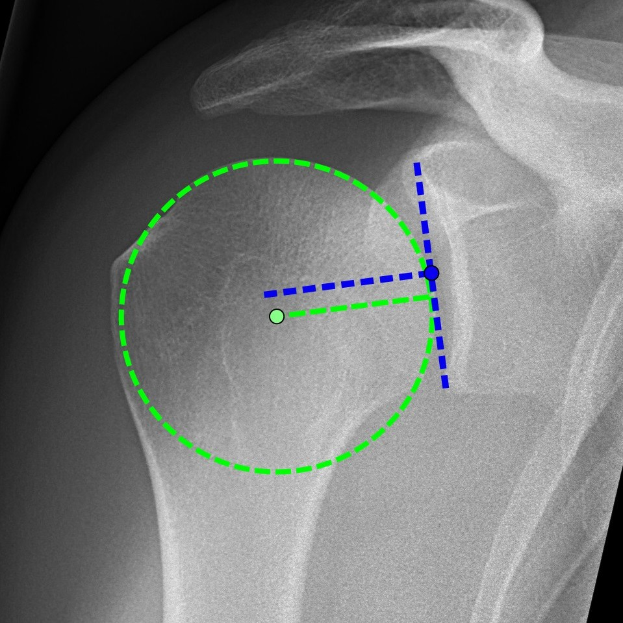

Ein Röntgenbild einer Schulter mit einem grünen Kreis, der ein Ligament in der Mitte markiert, umgeben von anderen Ligamenten.Miriam König

Den Auftakt bildete ein Vortrag von Dr. Tarik Akar, der anhand von Röntgen- und CT-Aufnahmen den ersten Fall vorstellte. Anschließend stabilisierten Chirurgen die Lendenwirbelsäule einer 41-jährigen Patientin mit Schrauben und Stäben – übertragen in Echtzeit aus dem OP-Saal des Krankenhauses Viersen.

Die zweite Operation demonstrierte die Implantation einer inversen Schulterprothese, die nach einer schweren Gelenkverrenkung die Beweglichkeit wiederherstellen sollte. Beide Eingriffe verfolgte das Publikum live mit.